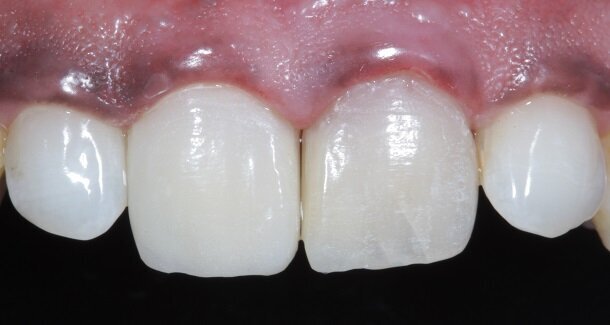

The figures show the clinical work flow involved. In the 1st appointment Oral prophylaxis, oral hygiene instructions were followed by an impression that was sent to the lab for a wax up [Fig 3 and 4]. In the subsequent appointments, Endodontic treatment was followed by Intra and extra coronal office bleaching using the Pola office bleaching kit. After two weeks, the shade stabilised post bleaching. Shade selection, rubber dam isolation and preparation was done on both the teeth to receive Direct composite veneers so as to close the midline diastema as well as correct the fractured teeth and the slight mal-alignment. Controlled Body Thickness (CBT) technique of layering was used with 3M Z350XT shades - Dentin shades A3, A2 and Enamel shades A2, clear translucent [Figures 5 to 11]. This was followed by the Finishing and polishing protocol as described in the figures.

Fig 22, 23 and 24 - In the post-rehydration follow-up appointment, the patient requested us to reduce the lengths of the central incisors slightly, and we reduced it by 0.5mm till he was satisfied.

A well polished direct restoration can add a lot of character to a patient's smile, last a good long time and all this, at a fraction of the cost of an indirect restoration. By strictly adhering to finishing and polishing protocols, we can achieve life-like restorations that are not easily discernible to the eye.